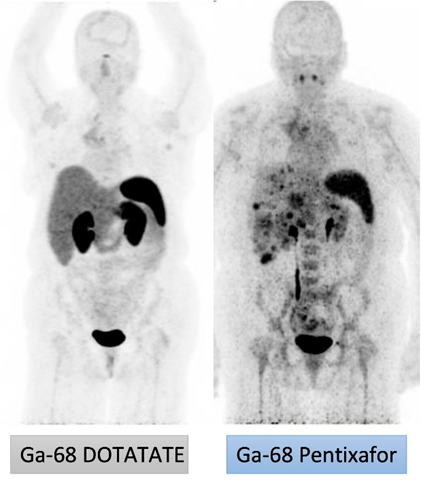

Yusuf Menda, MD (Clinical Co-Leader)Atypical carcinoids of the lung and lung neuroendocrine carcinomas (NECs) are currently incurable with most patients succumbing to disease within five years after diagnosis. This Project will pursue the development of an exciting new treatment paradigm for these cancers based on high LET alpha radioligand therapy (RLT) with 212Pb Pentixather targeting the CXCR4 receptor combined with cancer cell specific manipulations of metabolic oxidative stress. The studies will optimize clinical imaging, therapy delivery, and dosimetry techniques and, if successful, will have lasting impact on improving outcomes for neuroendocrine lung cancer patients.